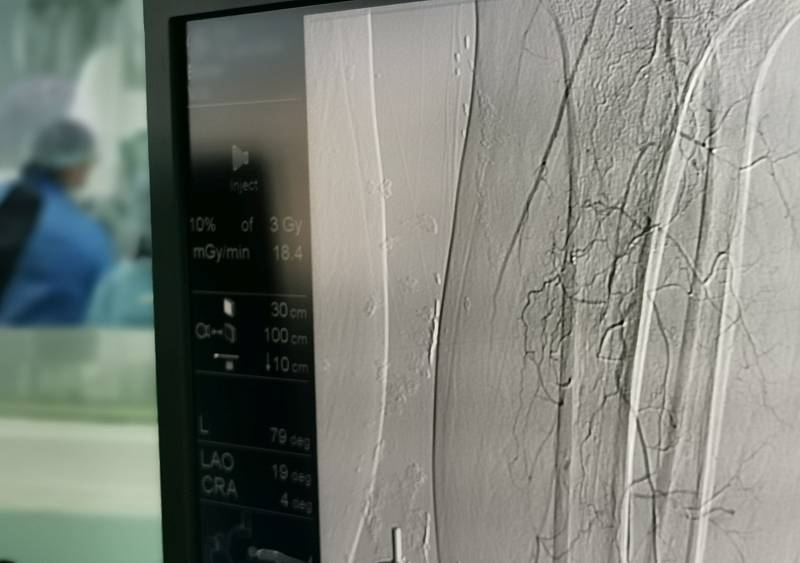

Операцию по расширению трахеи трехлетнему ребенку провели в краевой детской клинической больнице №1 города Владивостока. Ранее пациентам, которым необходима такая хирургическая манипуляция, приходилось лететь в Москву.

Как рассказали EastRussia в Минздраве Приморья, операция длилась несколько часов. Она проходила под руководством заведующего отделением эндоскопии Алексея Ткачука. С рождения у малыша была установлена специальная трубка в трахею (трахеостома) для того, чтобы он мог дышать. С помощью операции трахею расширили по всей длине. Сейчас врачи ожидают контрольных показателей.